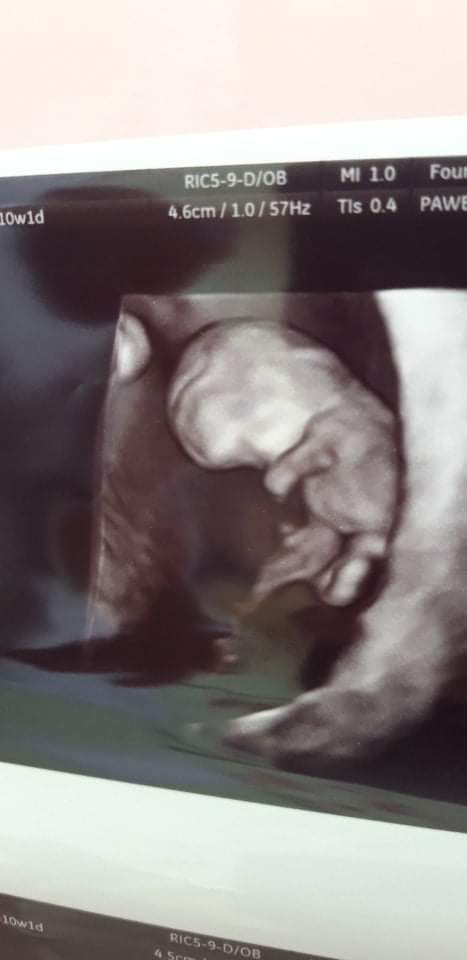

Żebyś nie musiała już szukać to wklejam ponowniepiszecie o.tym zdjęciu a dlaczego ja go nie widzę...juz chyba wczoraj probowalam do niego dotrzeć![]()

no już fajny dzidziolekŻebyś nie musiała już szukać to wklejam ponownie![]()